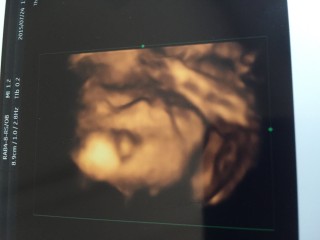

寝ててもバッチリカメラ目線(笑) 思わず先生も笑っていました(*´ω`*) 目は私似で鼻は旦那似かな? 可愛い♪